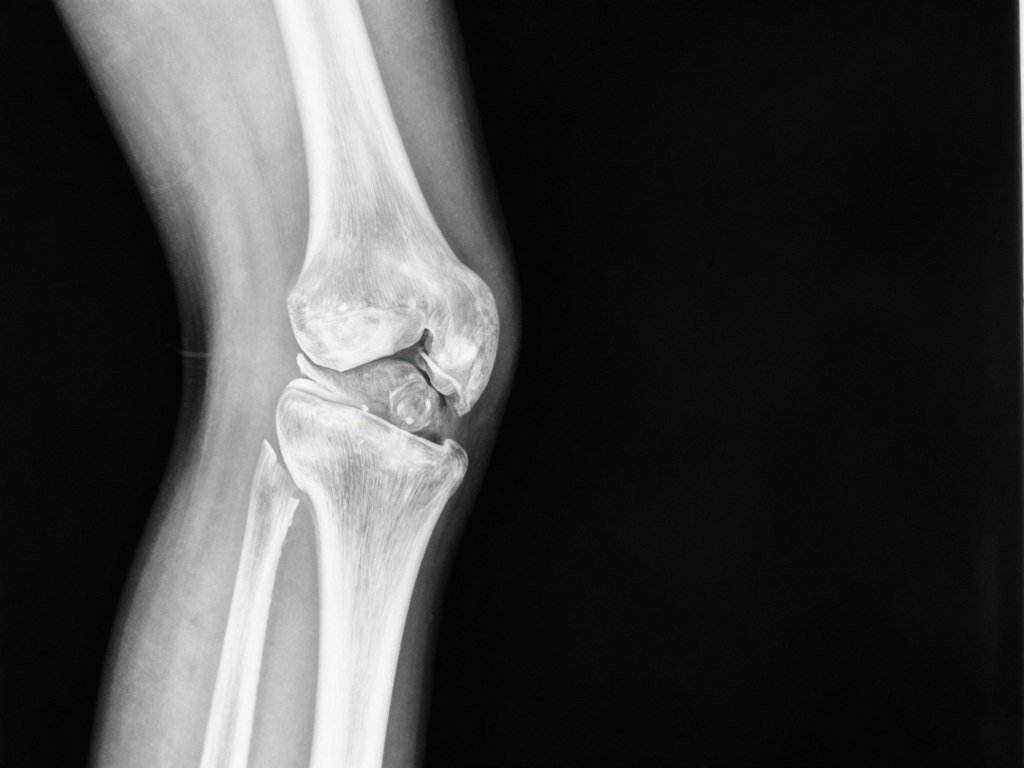

The Anatomy of a Knee & Common Causes of Pain

Think of your knee as a sophisticated hinge joint—but one that also rotates and glides. This complex structure consists of four

main components working together to support your body weight and enable movement:

- Bones: The femur (thigh bone), tibia (shin bone), and patella (kneecap) meet to form the knee joint.

- Cartilage: This slippery tissue covers the ends of bones and includes the meniscus, which acts as a shock absorber.

- Ligaments: These tough bands connect bones to other bones, providing stability to the joint.

- Tendons: These cord-like tissues connect muscles to bones, allowing movement when muscles contract.